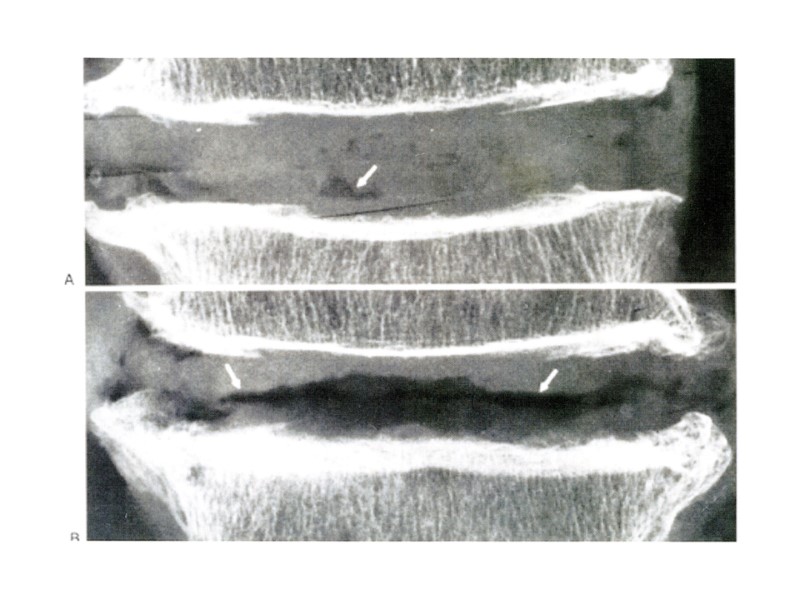

ИЗМЕНЕНИЯ НАДКОСТНИЦЫ Рентгенограмма голени Линейный периостит